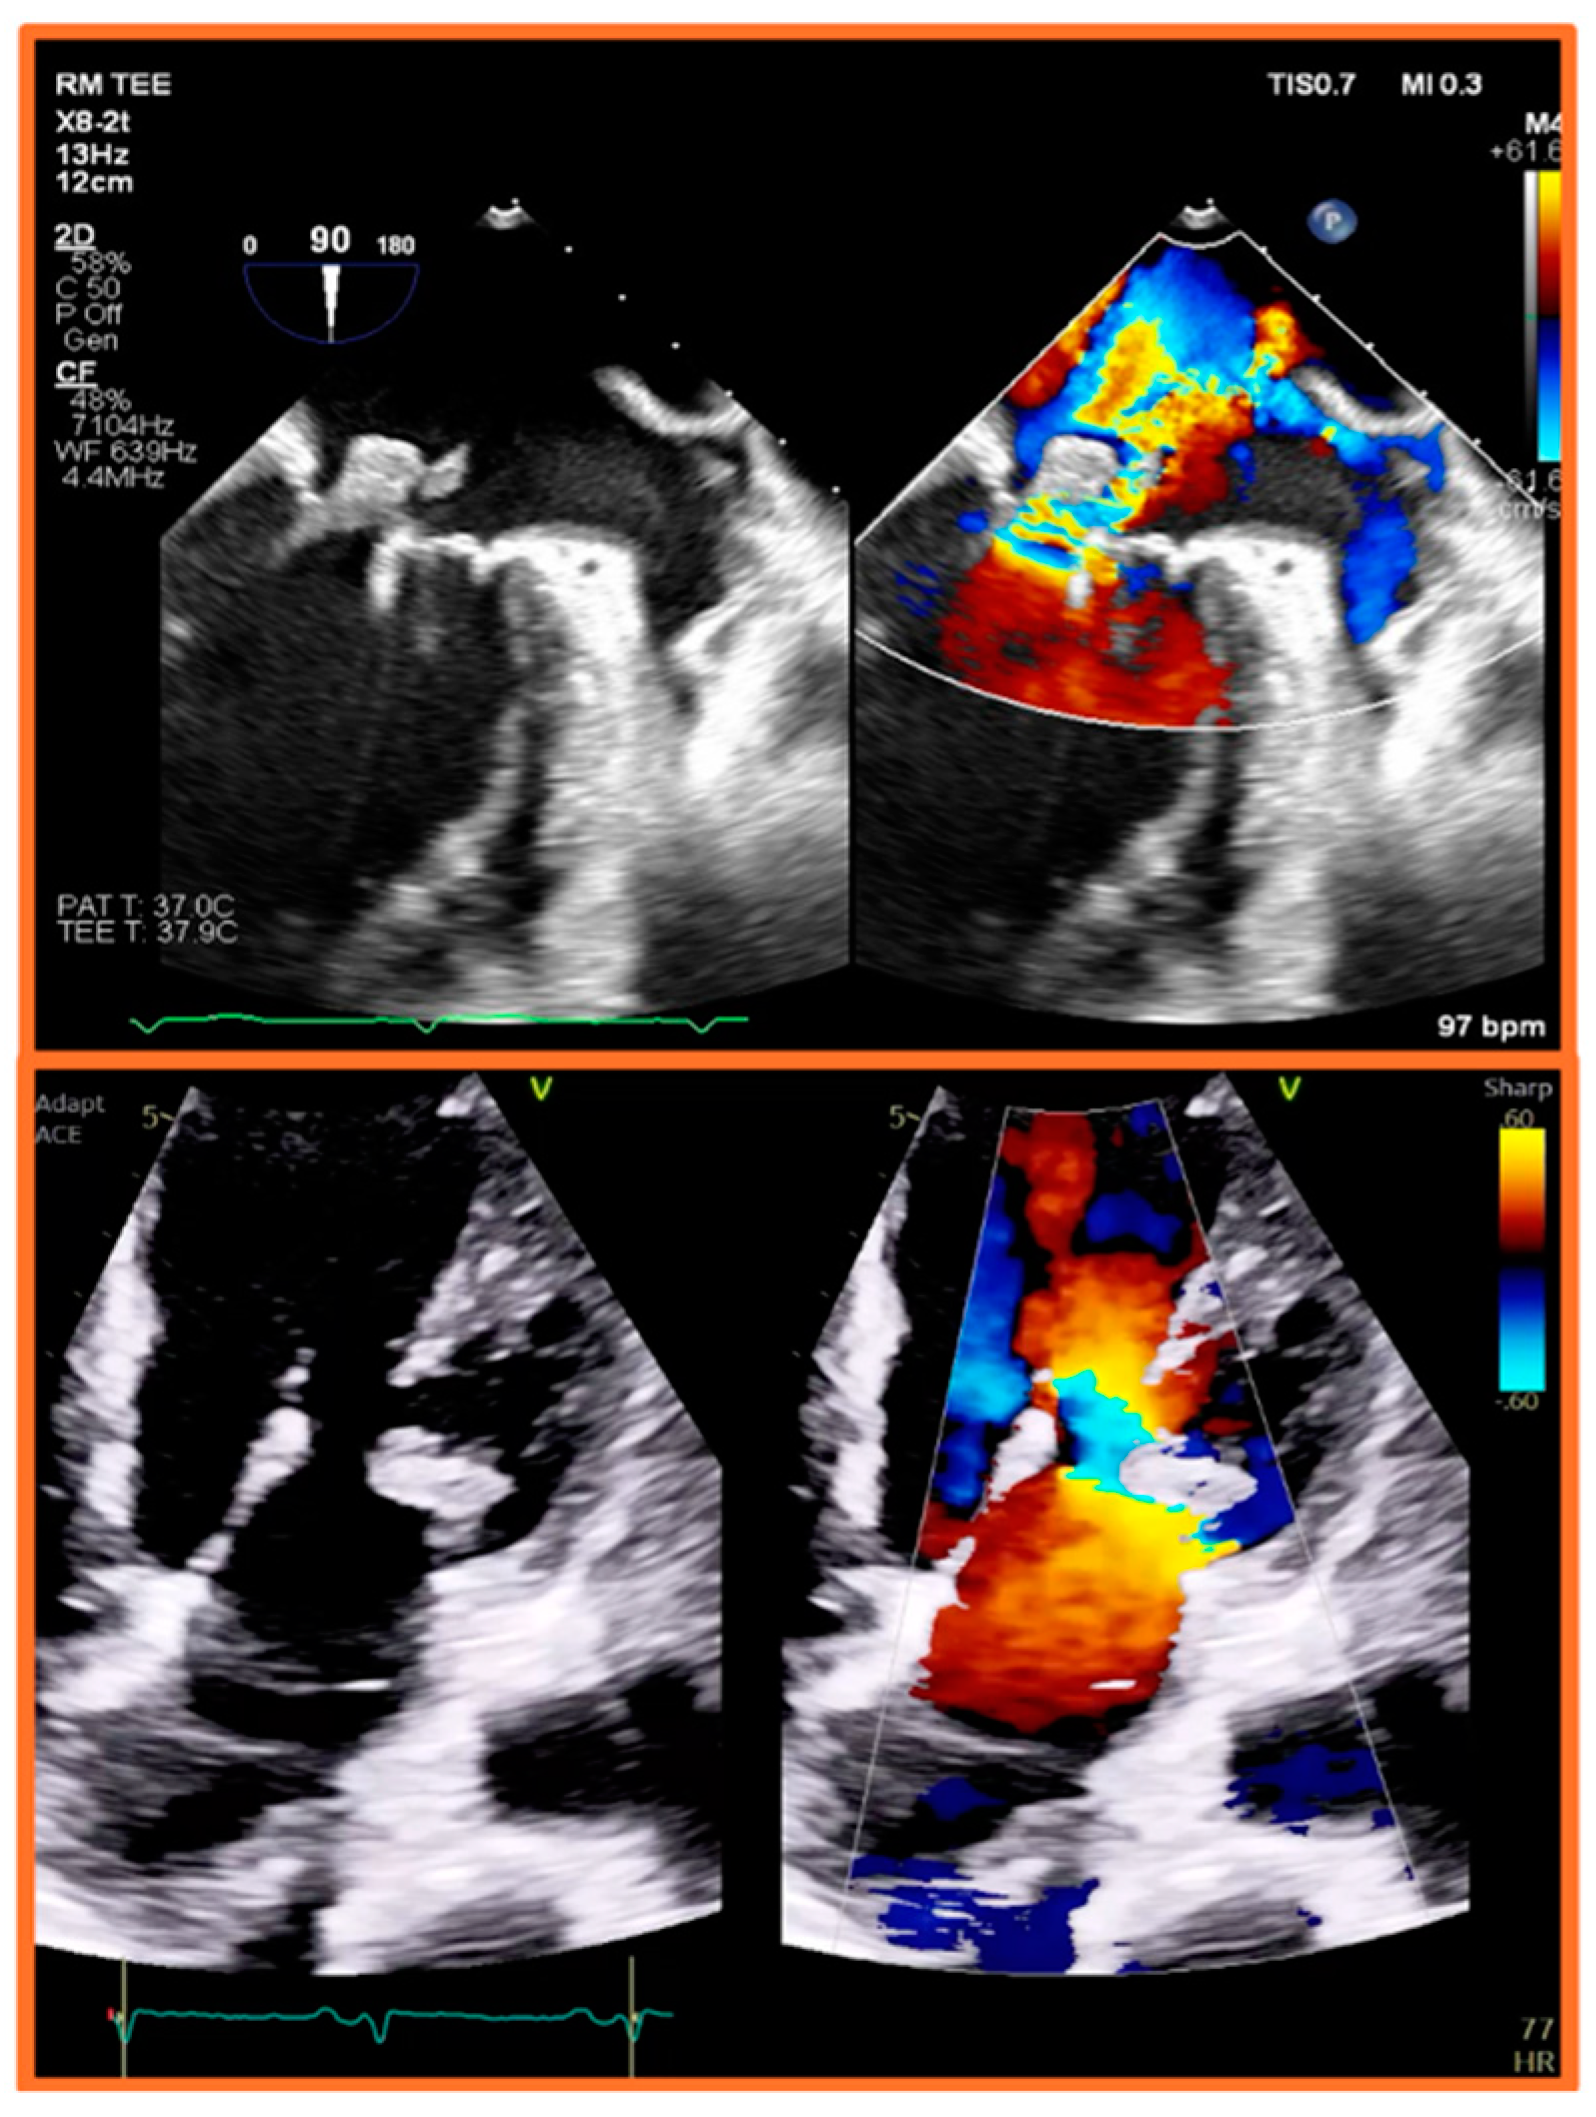

5.2. Transesophageal Echocardiography (TEE)